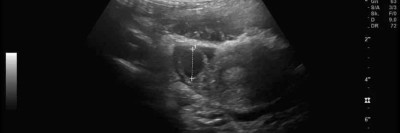

11-Jährige mit Bauchschmerzen: Was der Eileiter damit zu tun hat

Ein 11-jähriges Mädchen kommt mit rechtsseitigen Unterbauchschmerzen in die Notaufnahme. Labor-, Urin- und Ultraschalldiagnostik sind zunächst unauffällig. Erst in der zweiten Sonografie, nach einer erfolglosen Schmerztherapie, zeigt sich die seltene Ursache.

Bauchhoden/© Springer Medizin Verlag GmbH, Blutung im transversalen als auch im saggitalen Schnitt/© Institut für Diagnostische und Interventionelle Radiologie der Uniklinik Köln; mit freundlicher Genehmigung, Abdomensonographie: 14,7 mm große zystische Struktur im Bereich des rechten Ovars/© Isaev Y et al. / all rights reserved Springer Medizin Verlag GmbH, Röntgen einer Beckenfraktur und Abdomen-CT bei Jugendlichem/© Karvouniaris N. et al. / all rights reserved Springer Medizin Verlag GmbH, Drohende ösophago-arterielle Fistel nach Batterieingestion/© Lohmann J et al. doi.org/10.1007/s00101-024-01477-3 unter CC-BY 4.0, Kleinkind und Teddy mit Verband/© simoningate / Getty Images / iStock (Symbolbild mit Fotomodell), Akute Appendizitis/© Springer Medizin, Kind mit Gipsarm/© nycshooter / Getty Images / iStock (Symbolbild mit Fotomodell), Appendizitis /© Springer Medizin Verlag GmbH, Operationstechnik der Limberg-Plastik bei Sinus pilonidalis/© Jamal Driouch et al., Ärztin und Patientin im Gespräch/© andrei_r / Getty Images / iStock (Symbolbild mit Fotomodell), Bunte Plastikperlen/© Steven White / Getty Images / iStock, Ärztin betrachtet Röntgenbild/© dusanpetkovic1 / stock.adobe.com (Symbolbild mit Fotomodell), Search Icon, Knochensäge im Einsatz bei Knie-TEP/© Issara / stock.adobe.com (Symbolbild mit Fotomodellen), Hirntumoren sichtbar im MRT/© semnic / Getty Images / iStock (Symbolbild mit Fotomodell), Lungentrainer/© S@photo / stock.adobe.com (Symbolbild mit Fotomodell)